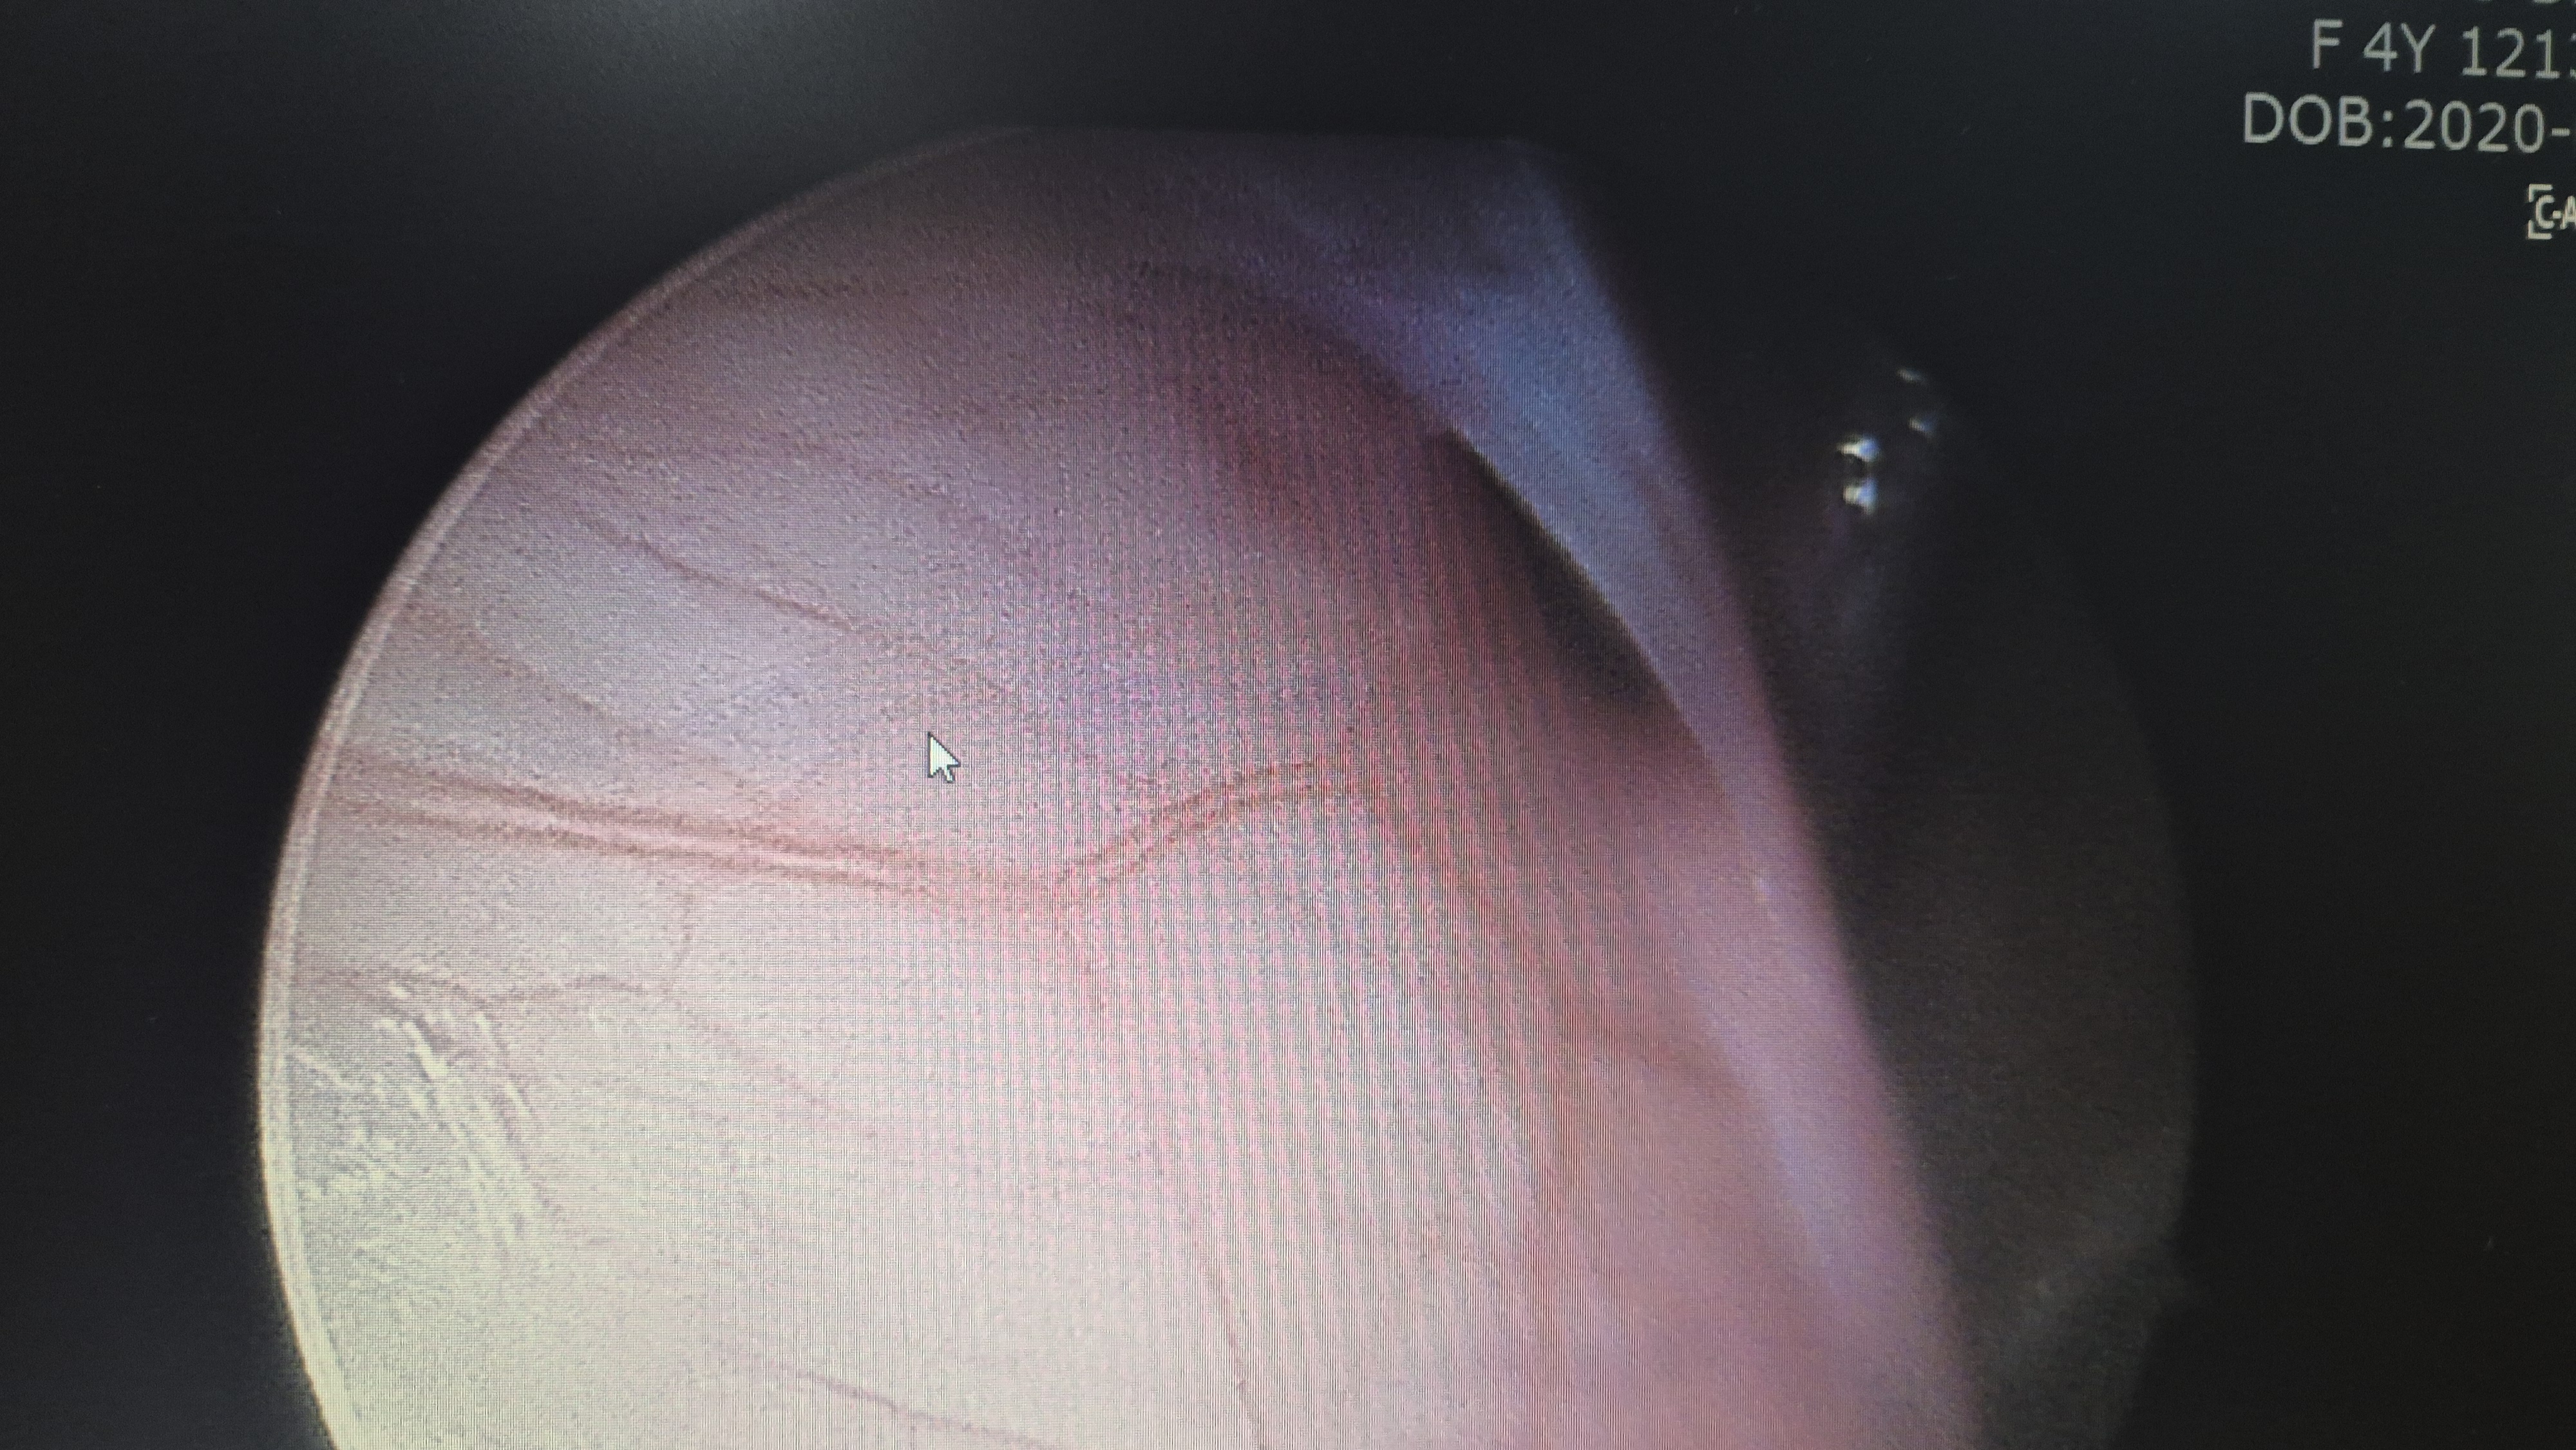

좌측 탈장 교정 후 사진.

우측 탈장 교정후 사진.